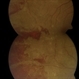

- progressive outer retinal necrosis (PORN)

- Fundus camera

- Fundus photography of an 38-year-old man diagnosed with PORN.